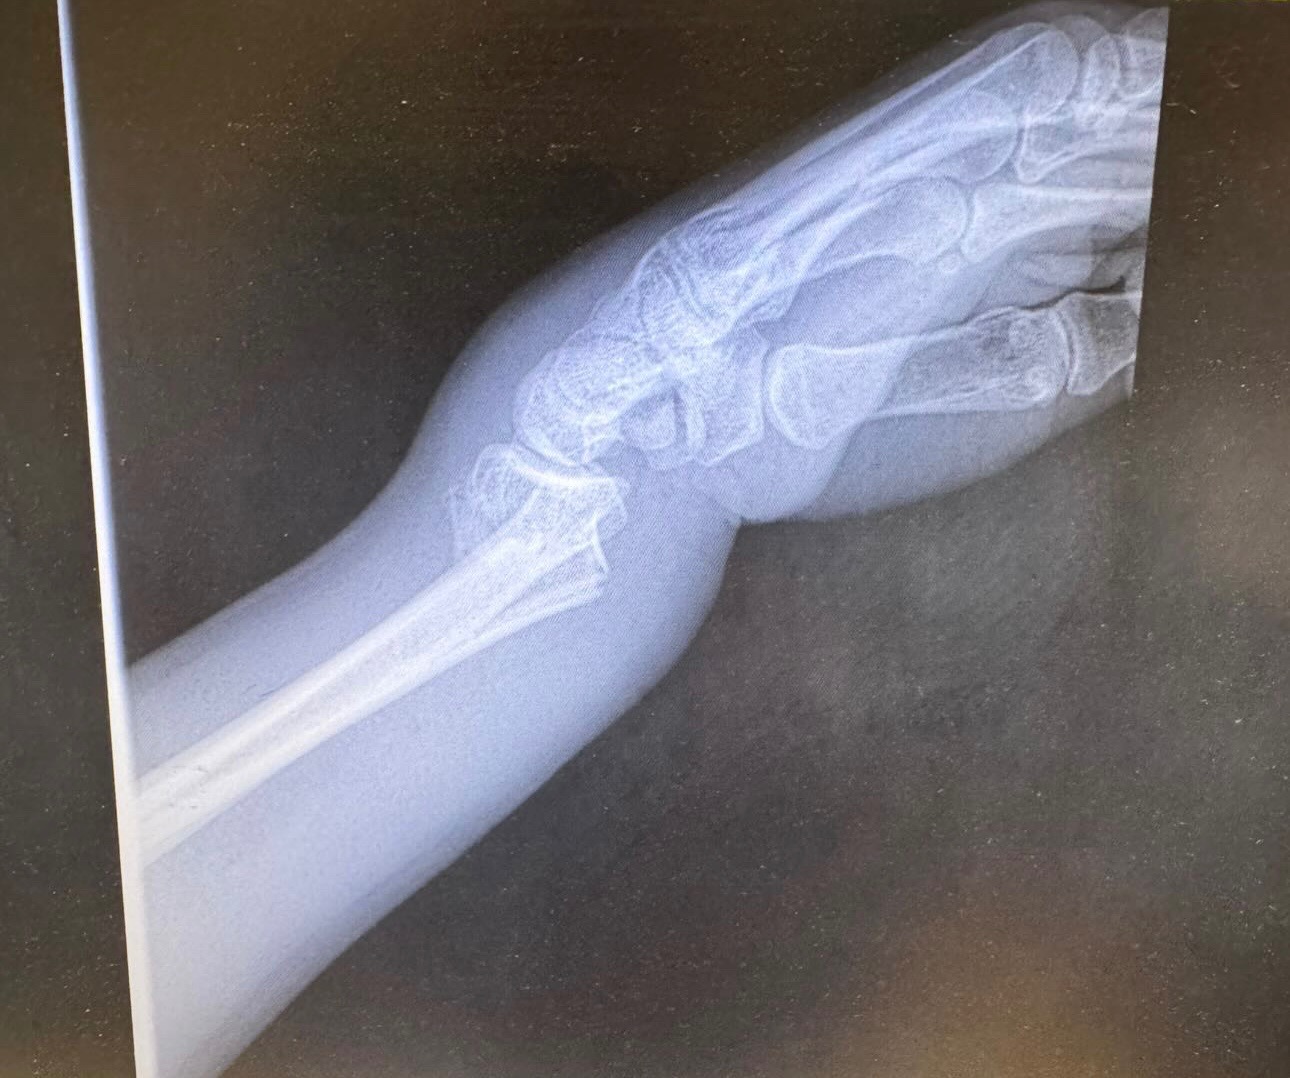

Lyla was killed by the impact. My sister survived, but she has suffered a devastating injury: her wrist is broken in three places. She may require surgery and will find out in the coming week.